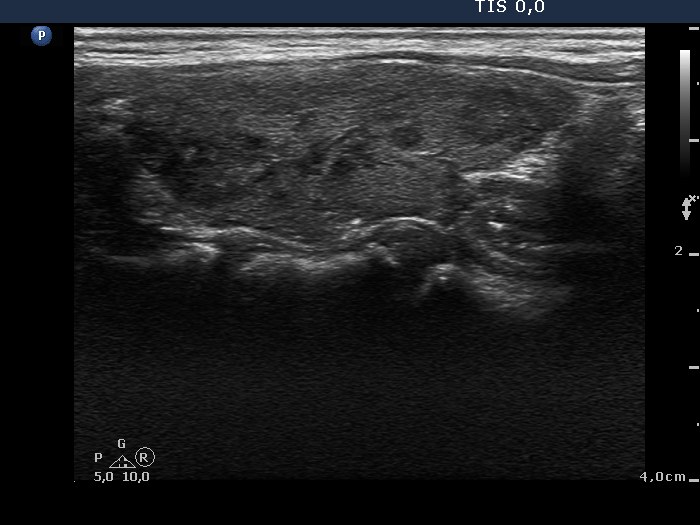

Ultrasonography: the thyroids were composed of hypoechogenic areas not fitting a nodule. The vascularization was significantly increased in the right, while decreased in the left lobe.